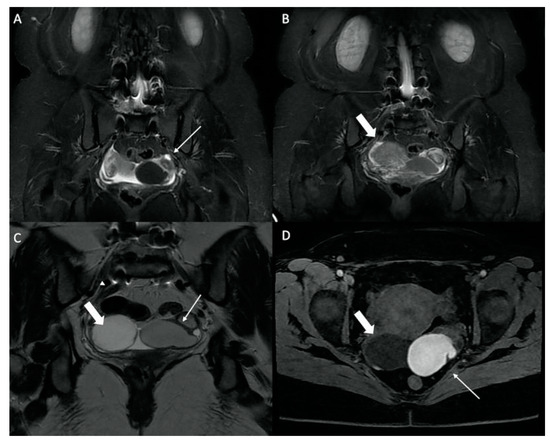

| Hip Joint | Congestive hip osteoarthritis | 17 |

| Stress femoral fracture | 4 | |

| Avascular femoral osteonecrosis | 1 | |

| Extensive acetabular edema | 1 | |

| Gluteal Muscles | Gluteal tendinobursitis | 21 |

| Sacroiliac Joint | Congestive degenerative arthropathy | 10 |

| Inflammatory sacroiliitis | 4 | |

| Sacral fracture | 1 | |

| Pubis | Septic arthritis of the pubis | 1 |

| Femur | Periprosthetic loosening fracture (total hip replacement) | 1 |

| Greater trochanter fracture | 1 | |

| Mixed Musculoskeletal Causes | Inflammatory sacroiliitis and gluteal tendinobursitis | 1 |

| Degenerative congestive sacroiliac arthropathy and gluteal tendinobursitis | 1 | |

| Others | Endometrioma with posterior deep pelvic endometriosis | 1 |

| Ischio-femoral impingement | 1 | |

| Retroperitoneal mass syndrome with urinary obstruction | 1 |